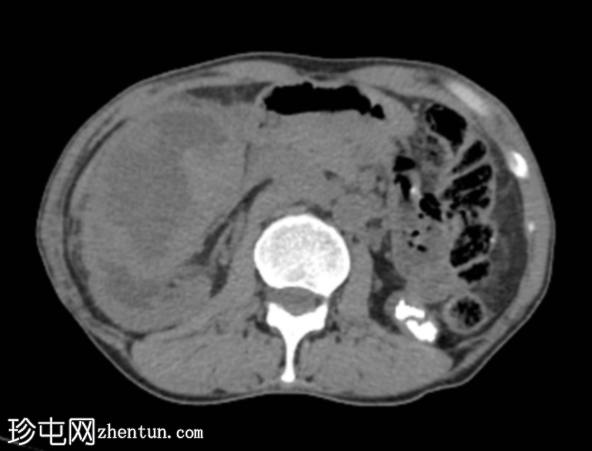

CT

轴位

平扫

右肾前部可见一边界清晰的外生性病变,呈异质性,包含实性及囊性成分,内部可见多发结石。肾周可见模糊影。

左肾体积缩小且萎缩,可见多发结石。

病变内部存在结石及肾周模糊影提示炎症性病变,可能为局灶性黄色肉芽肿性肾盂肾炎(XGP),而非肿瘤性肿块(肾细胞癌)。